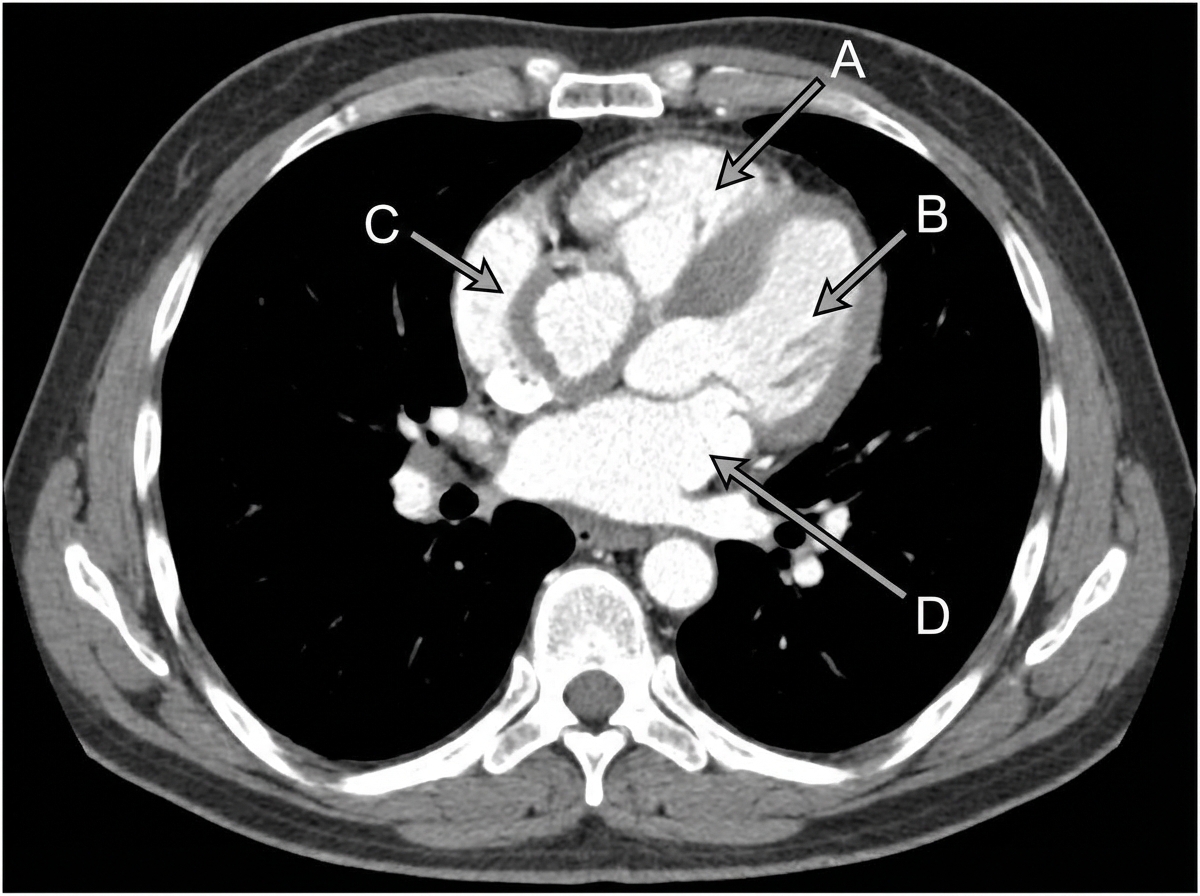

In a CT scan of the thorax, which labeled site or structure becomes hypertrophied as a result of pulmonary stenosis?

Explanation: ***Site C (Right Ventricle)*** - **Pulmonary stenosis** causes increased **right ventricular outflow resistance**, forcing the right ventricle to work harder and leading to **right ventricular hypertrophy**. - On CT scan, this appears as **thickened right ventricular wall** and increased muscle mass to compensate for the stenotic pulmonary valve. *Site A* - Likely represents the **left ventricle**, which is not directly affected by pulmonary stenosis as it pumps blood to the **systemic circulation**. - **Left ventricular hypertrophy** would occur in conditions like **aortic stenosis** or **systemic hypertension**, not pulmonary stenosis. *Site B* - Probably indicates the **right atrium** or **left atrium**, which may show mild dilation but not hypertrophy in pulmonary stenosis. - Atrial chambers primarily serve as **blood reservoirs** and do not develop significant muscular hypertrophy like ventricles. *Site D* - Most likely represents the **left atrium** or **aorta**, structures unrelated to the pulmonary circulation pathway. - These structures remain **anatomically normal** in isolated pulmonary stenosis as they handle systemic rather than pulmonary blood flow.